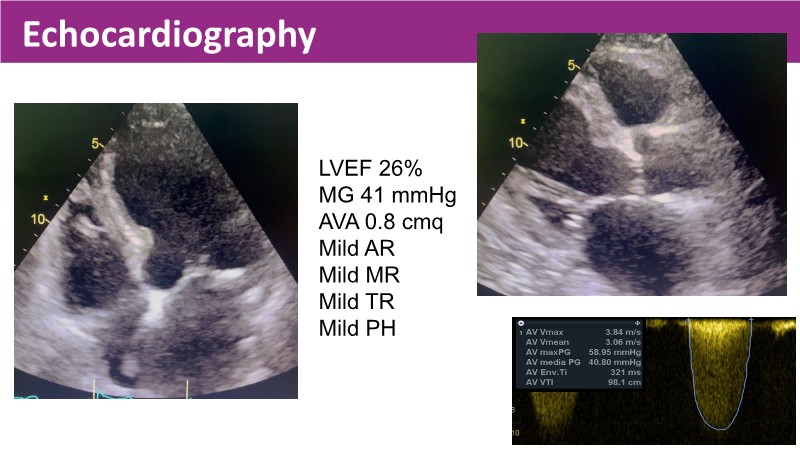

Discover the latest insights from the Myval THV series in this session from PCR London Valves 2025. Through real-world, case-based learning, the session explores lifetime management strategies for TAVI patients, the clinical relevance of intermediate and extra-large valve sizing, and the impact of foreshortening on accurate valve deployment.

Key presentations cover matching prostheses to patient anatomy, the importance of predictable valve performance in challenging situations, and pivotal trial data supporting Myval THV outcomes. Highlights include the OCTAPRO+ THV’s progressive design enabling precise deployment, the OctaAlign technique for commissural alignment, and next-generation strategies to optimize lifetime TAVI management.